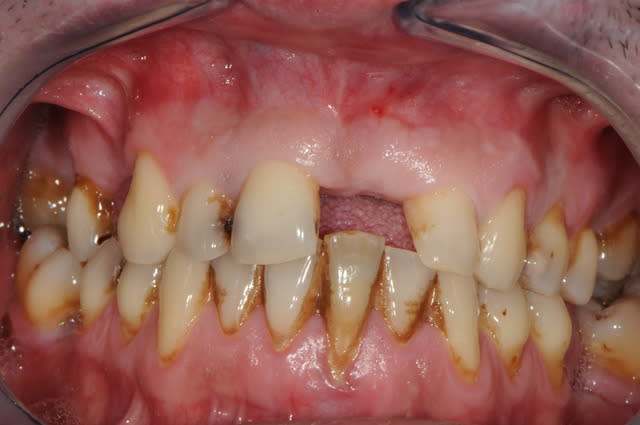

Il y a aussi un gummy-smile et un sourire inversé, dommage après tant de couronnes.

The final result is a gummy smile with reverse smile line...too bad after all those crowns. A simple perio surgery could have give better result.